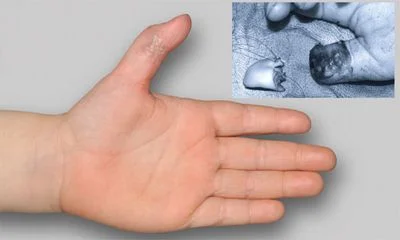

gegen das Personal richtet. Verbale Anfeindungen, Beschimpfungen

und sogar Drohungen gehören für viele Beschäftigte inzwischen zum

Alltag.

Aggressionen und fehlendes Verständnis

Ein weiteres Problem ist die zunehmende Aggressivität einiger Patienten. Lange Wartezeiten, Überforderung und persönliche Krisen entladen sich immer häufiger in Wut und Unverständnis. Dabei gerät aus dem Blick, dass das Personal nicht Ursache, sondern selbst Opfer der Überlastung ist. Sicherheitsdienste müssen immer öfter eingreifen, um Eskalationen zu verhindern.